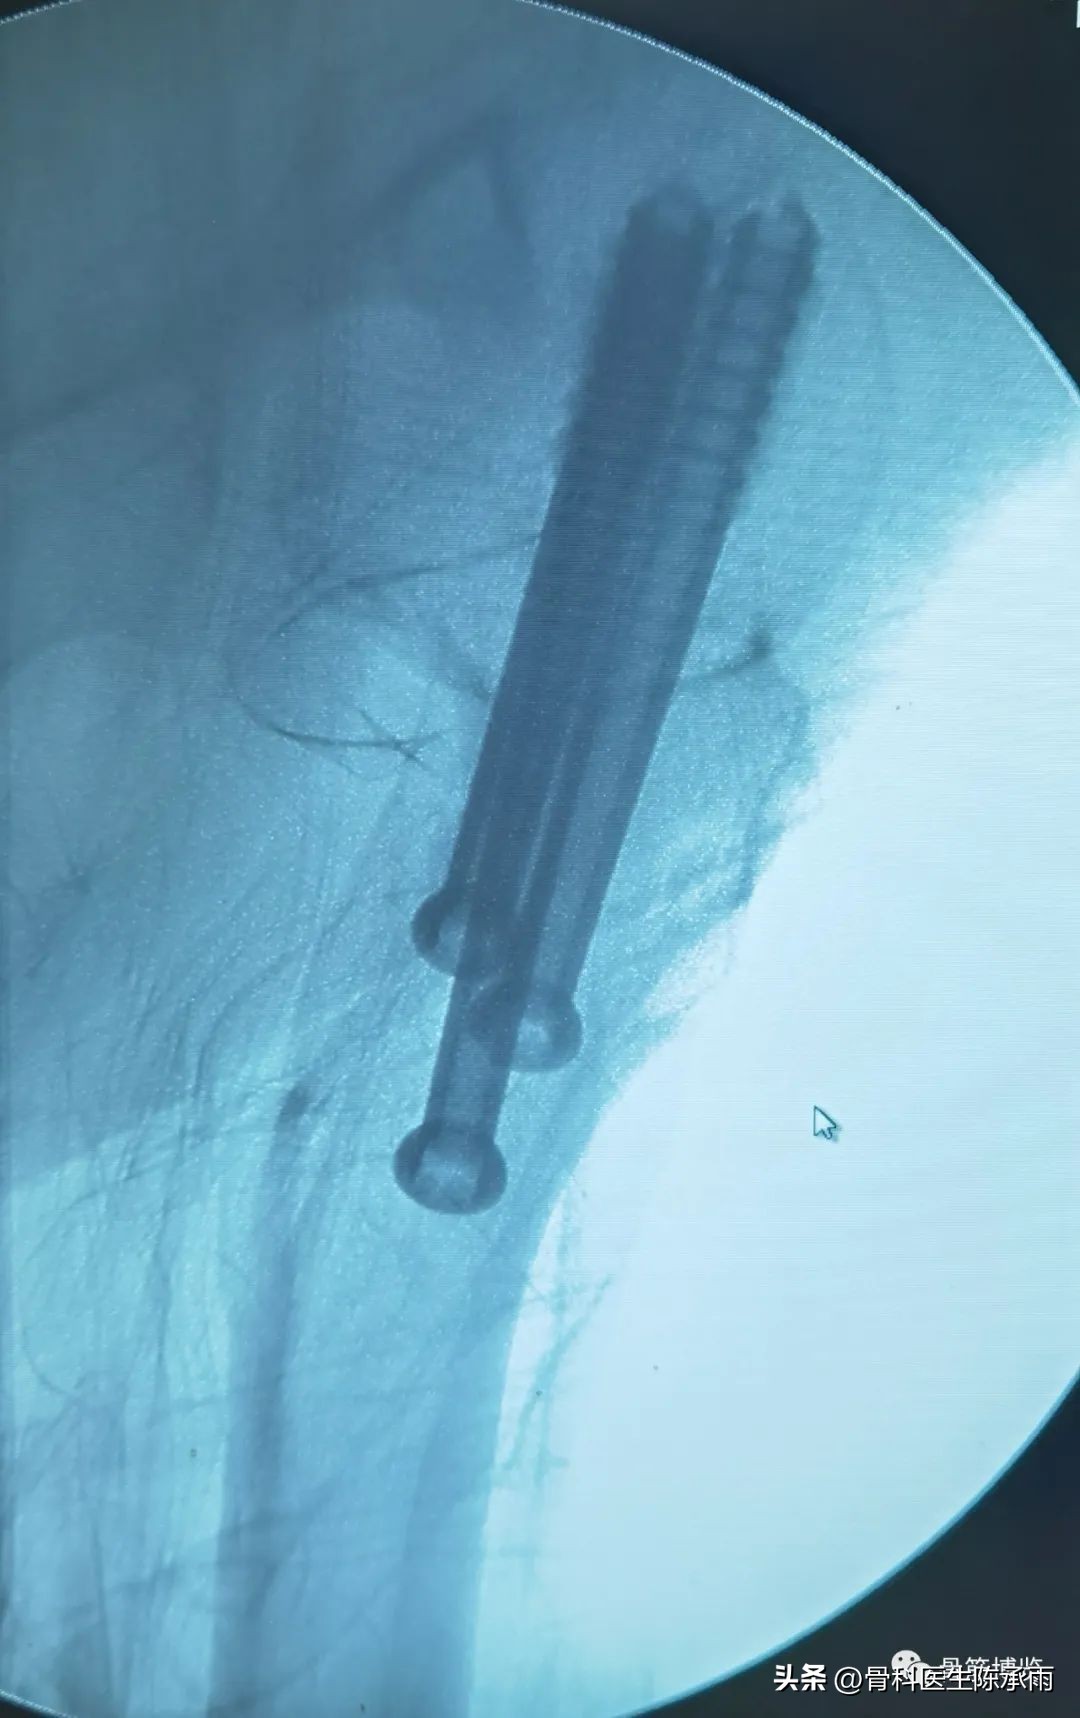

常规股骨颈骨折相对简单

术后复查